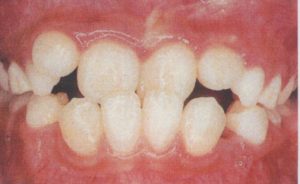

現在幼稚園に通う5歳の女の子は、ちょうど上下顎の前歯が萌出を終えるあたりでした。

しかし、残念なことに、被蓋ば逆転して萌出しており、いわゆる前歯部反対咬合でした。

上下顎の前歯が多少混雑する程度でしたら、幼稚園の周りのお子さんと比べてもそれ程心配するほどでなかったかもしれませんが、

反対咬合は一般の方にも異常の程度が非常にわかりやすい不正だと言えます。